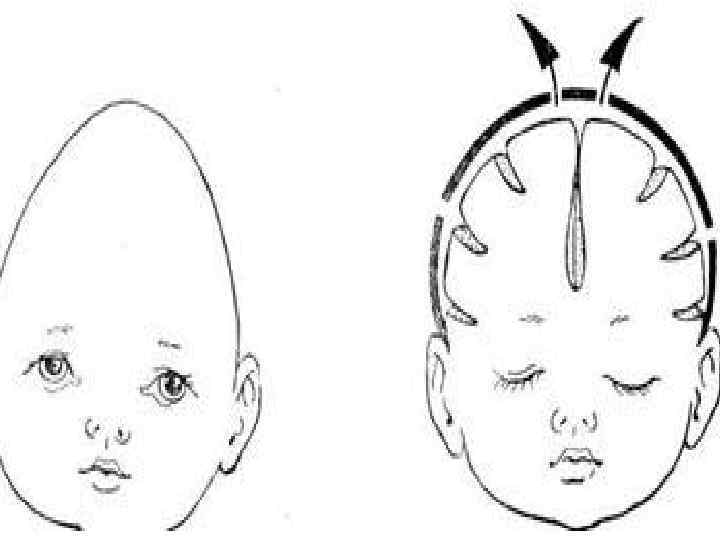

Лечение краниостеноза Краниостеноз — преждевременное заращение одного, нескольких или всех швов между костями черепа ребенка, что ведет к его деформации и повышению внутричерепного давления. В раннем периоде аномалии развития костей черепа часто сопровождаются пороками развития головного мозга или препятствуют его дальнейшему развитию. Частота появления краниостеноза 1 на 1000 новорожденных. Причины возникновения до конца не выяснены: среди факторов называют как внешние факторы, так и наследственную предрасположенность. Диагноз устанавливается на основании характерных изменений строения черепа, данных рентгенологического и офтальмологического обследования. Суть оперативного лечения — ремоделирование костей черепа. Для фиксации ремоделированных костей обычно используют титановые минишурупы и минипластины, а также проволочные швы; фиксирующие конструкции убирают через 1 год после операции. Но в последнее время появилась возможность использовать саморассасывающиеся фиксирующие материалы, что значительно облегчает лечение маленьких пациентов. Со временем такие материалы самозаменяются 107 собственной костью человека